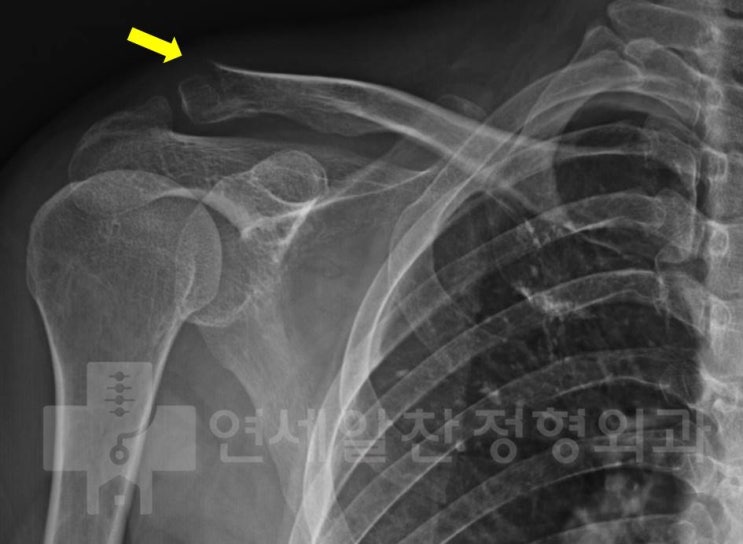

쇄골 골절 후 발생된 외상 후 유착성 관절낭염에 대한 관절수액팽창술 및 재활의 결과

38세 여자 환자로 3개월전 쇄골 골절 진단 받은 후 velpeau bandage 를 하여 보전적 치료를 한 후 골절 유...

2017. 12. 20.